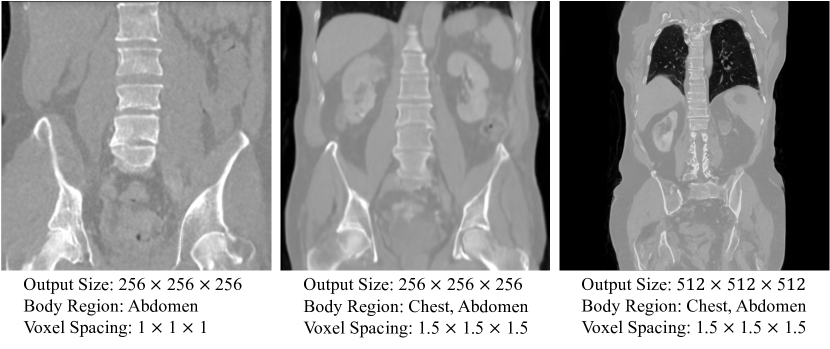

Response to primary conditions : Body regions, voxel spacing condition에 맞게 높은 flexibility와 control을 보여줌.